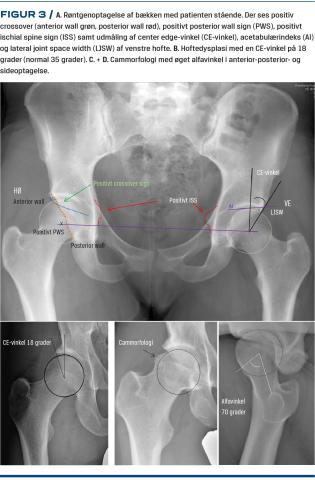

Vurdering af patoanatomiske forhold på røntgenbilleder

Artrose vurderes efter Tönnis’ klassifikation [17] eller ved måling af lateral ledspaltehøjde (LJSW) [18] (Figur 3). Tönnis grad 2-3 eller ledspaltehøjde < 3 mm er tegn på degenerative bruskforandringer. Acetabulums dækning af caput femoris vurderes med center-hjørne-vinkel (CE-vinkel) og acetabulærindeks (AI). Den normale CE-vinkel er i gennemsnit 35 grader, mens en værdi < 20 grader er udtryk for hoftedysplasi og intervallet 20-25 grader betegnes borderlinedysplasi. AI > 10 grader er udtryk for en stejl acetabulum, hvilket er et element i hoftedysplasi. Acetabulærretroversion betyder, at acetabulums åbning vender mere bagud end normalt, hvilket man får mistanke om, hvis der er posterior wall sign, crossover og ischial spine sign.

En camdeformitet, som typisk ligger i overgangen mellem collum og caput femoris, kan vurderes på bækkenbilledet, men den påvises bedst på en sideoptagelse eller andre specialoptagelser. Graden af udbygning måles med alfavinklen. Mange bruger en alfavinkel > 55 grader hos kvinder og > 68 grader hos mænd som grænse for radiologisk relevant FAIS [19].